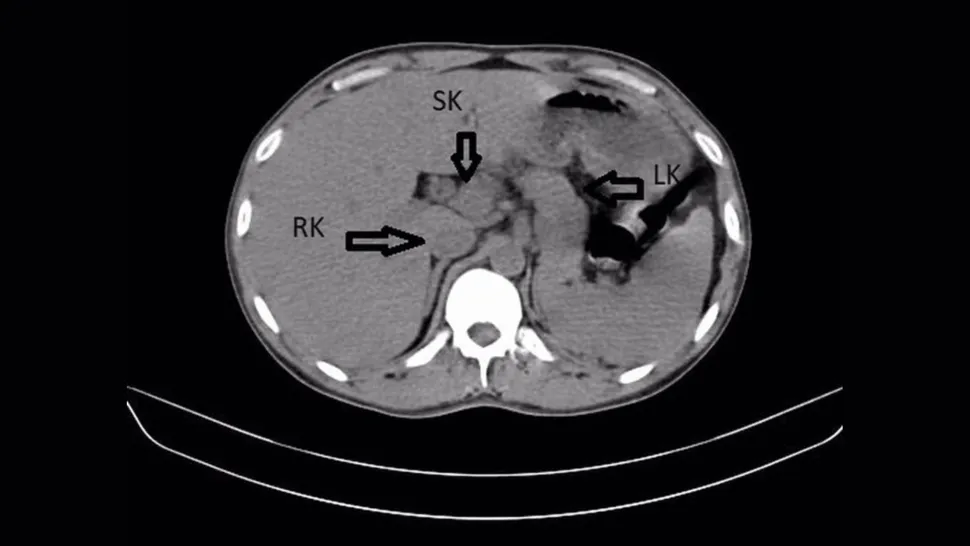

Анализы сразу подтвердили бактерию клебсиеллу пневмонии, которая вызвала воспаление. Чтобы разобраться до конца, специалисты провели компьютерную томографию. На снимках вместо двух почек оказалось три. Дополнительная почка плотно срослась с правой в форме подковы, и в ней тоже шло воспаление.